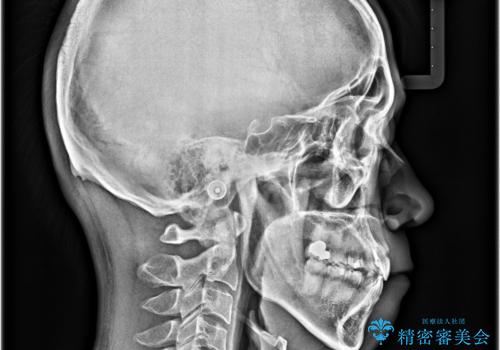

上下の前歯部に強い叢生(ガタガタの歯並び)があり、そのまま歯を並べると出っ歯になってしまう可能性がありました。

そこで、上下左右の第一小臼歯を抜歯し、歯が並ぶためのスペースを確保し叢生を解消する治療計画を立てました。

八重歯はきれいに整い、前歯もバランスよく収まり、横顔のラインも自然に改善されました。